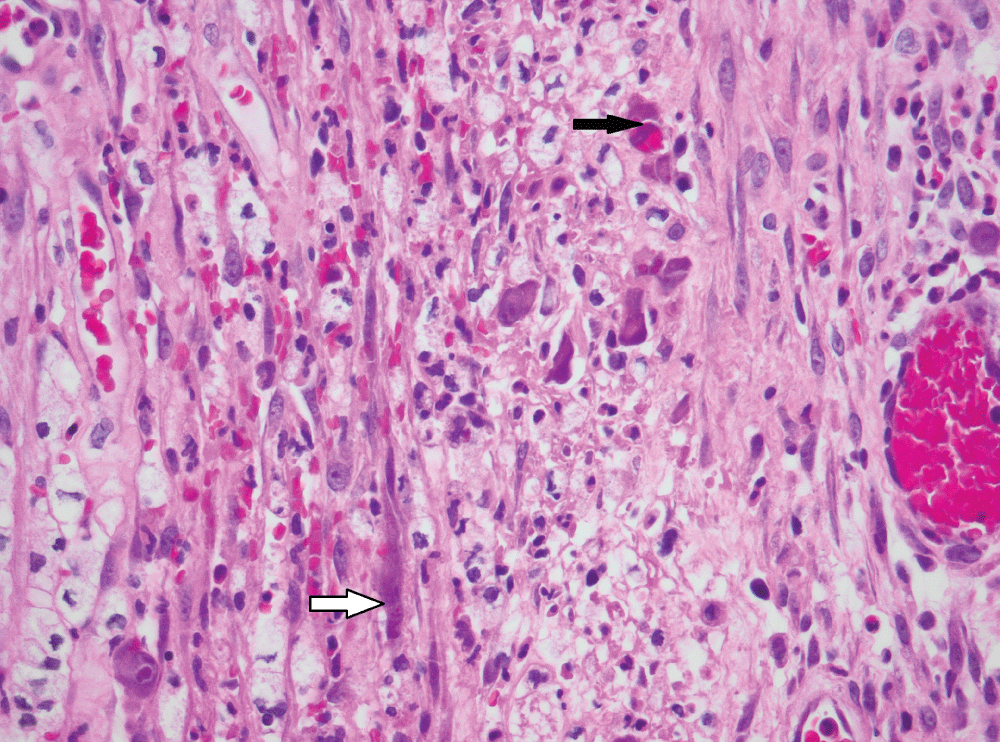

The histological findings are presented in Table 2. Most biopsies (n = 40) showed severe inflammation with ulceration. Scanty CMV infected cells were noted in 30 biopsies, moderate in 15 and heavy loads were noted in 13 biopsies (Figure 1). There was no correlation between the quantity of CMV infected cells and the degree of inflammation (p = 0.828). The cell type most frequently infected was endothelium (n = 50). Of the 5 cases with infection of smooth muscle, 3 had bowel perforation (Figure 2). Crypt epithelial cells were infected in seven cases and surface mucosae were never infected. CMV IHC was performed in a total 31 biopsies (53.5%), 32.3% of these stains were negative. All IHC negative cases had scant CMV inclusions on H&E that were cut away on the level for IHC. An additional aetiopathogen was noted in 8 (13.8%) biopsies. Cryptosporidium was noted in one case of CMV in the colon, one in the stomach (Figure 3) and another in the small intestine. Helicobacter were noted in 3 gastric biopsies that also showed evidence of CMV infection. One oesophageal biopsy also showed Candida and a small intestinal biopsy showed mycobacterial infection.

Figure 2: CMV infection of smooth muscle cells (white arrow) and endothelial cells (black arrow) in bowel removed for perforation (original magnification, x400). View Figure 2